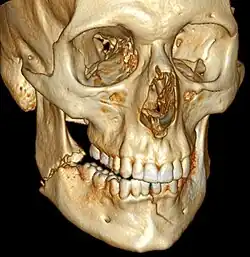

3D computed tomographic image of a mandible fracture in two places. One is a displaced right angle fracture and the other is a left parasymphyseal fracture. | |

Computed tomography is the most sensitive and specific of the imaging techniques. The facial bones can be visualized as slices through the skeletal in either the axial, coronal or sagittal planes. Images can be reconstructed into a 3-dimensional view, to give a better sense of the displacement of various fragments. 3D reconstruction, however, can mask smaller fractures owing to volume averaging, scatter artifact and surrounding structures simply blocking the view of underlying areas.